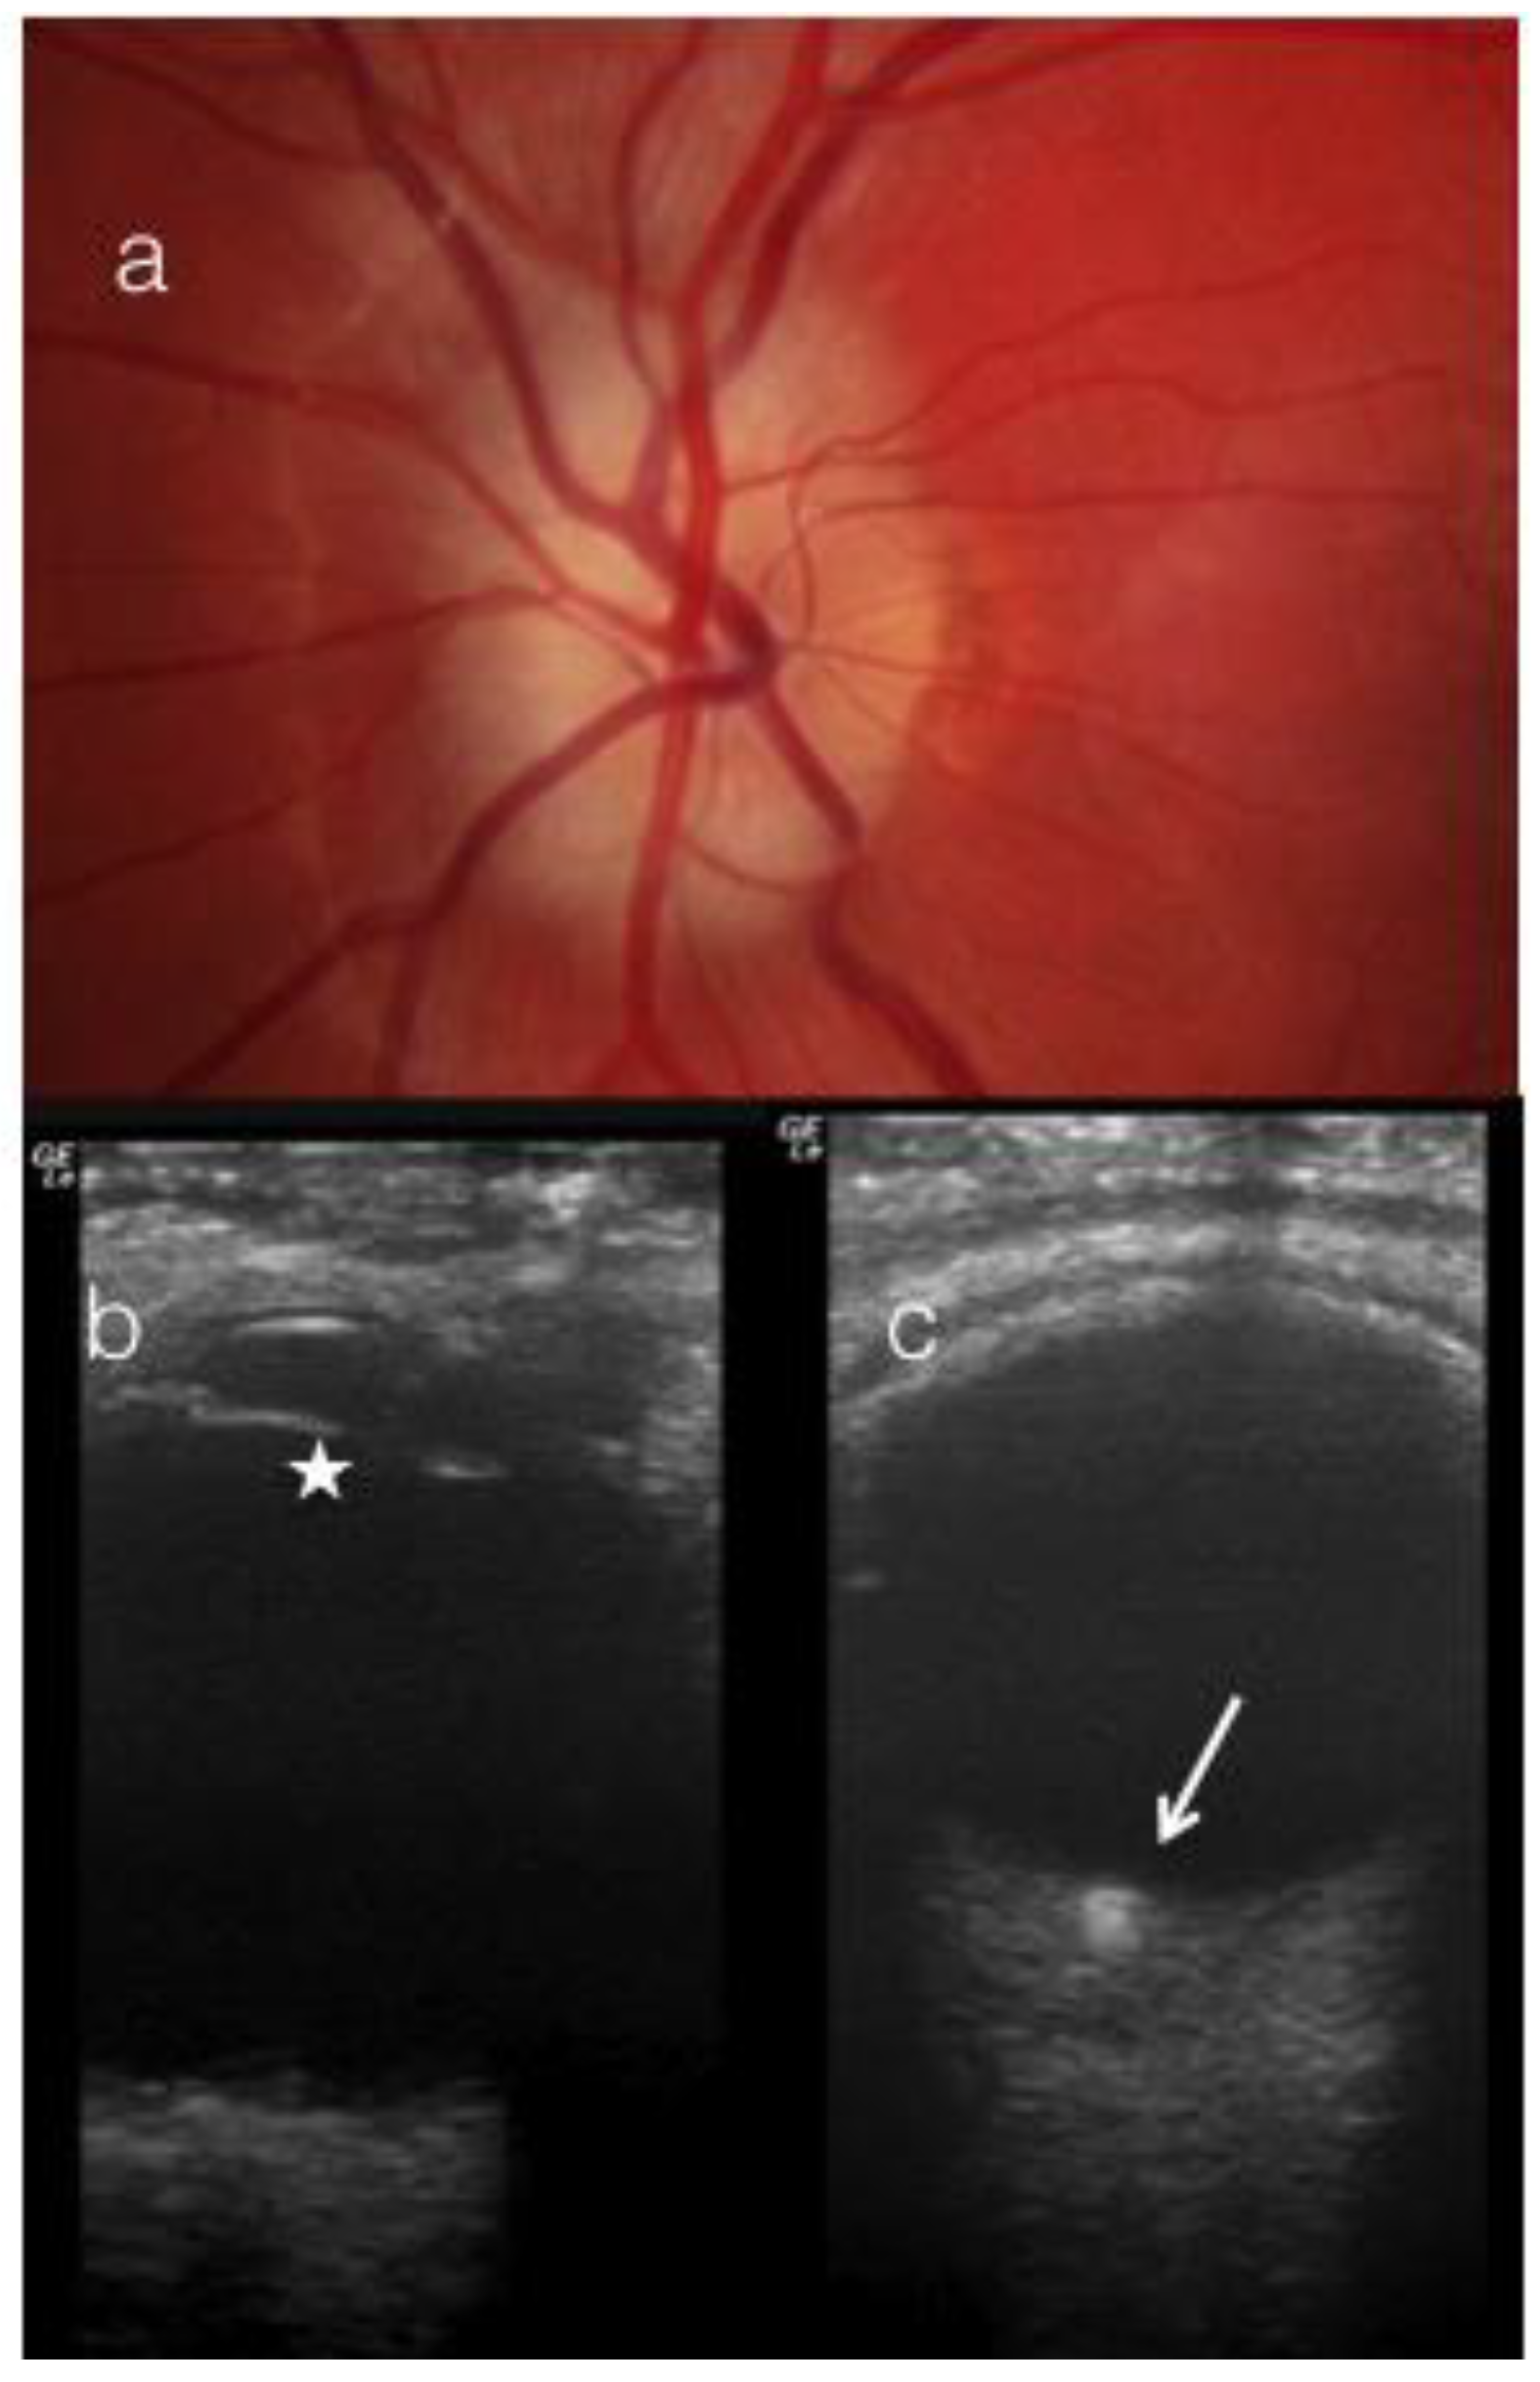

Buried optic disc drusen (a) was detected as nodular and... Download Optic Disc Drusen Radiology The most accredited theory is that they. Features are those of optic disc. Optic disc drusen (odd) are autofluorescent, calcified deposits found in the optic nerve head, and typically occur in small,. Optic nerve drusen are refractive, calcified nodules located within the optic nerve head. A tiny calcific spot is noted at the anatomical site of the optic disc bilaterally,. Optic Disc Drusen Radiology.

Computed tomography scan of optic nerve head showing calcification of Optic Disc Drusen Radiology Features are those of optic disc. The most accredited theory is that they. A tiny calcific spot is noted at the anatomical site of the optic disc bilaterally, no mass is seen on either side. Optic nerve drusen are refractive, calcified nodules located within the optic nerve head. Optic disc drusen (odd) are acellular deposits in the prelaminar optic nerve. Optic Disc Drusen Radiology.